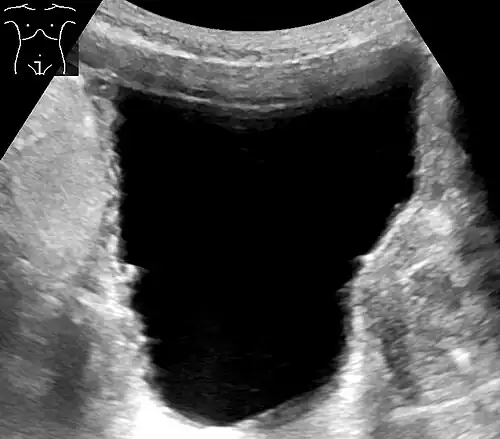

Analysis of urine flow may aid in establishing the type of micturition (urination) abnormality. Common findings, determined by ultrasound of the bladder, include a slow rate of flow, intermittent flow, and a large amount of urine retained in the bladder after urination. A normal test result should be 20–25 ml/s peak flow rate. A post-void residual urine greater than 50 ml is a significant amount of urine and increases the potential for recurring urinary tract infections. In adults older than 60 years, 50-100 ml of residual urine may remain after each voiding because of the decreased contractility of the detrusor muscle.[7] In chronic retention, ultrasound of the bladder may show massive increase in bladder capacity (normal capacity is 400-600 ml).